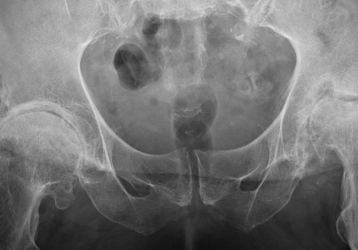

Хирургическая операция для лечения импиджмент-синдрома тазобедренного сустава

Суть и особенности хирургического лечения импиджмент-синдрома тазобедренного сустава, виды операций при феморо-ацетабулярном импиджменте, стоимость.